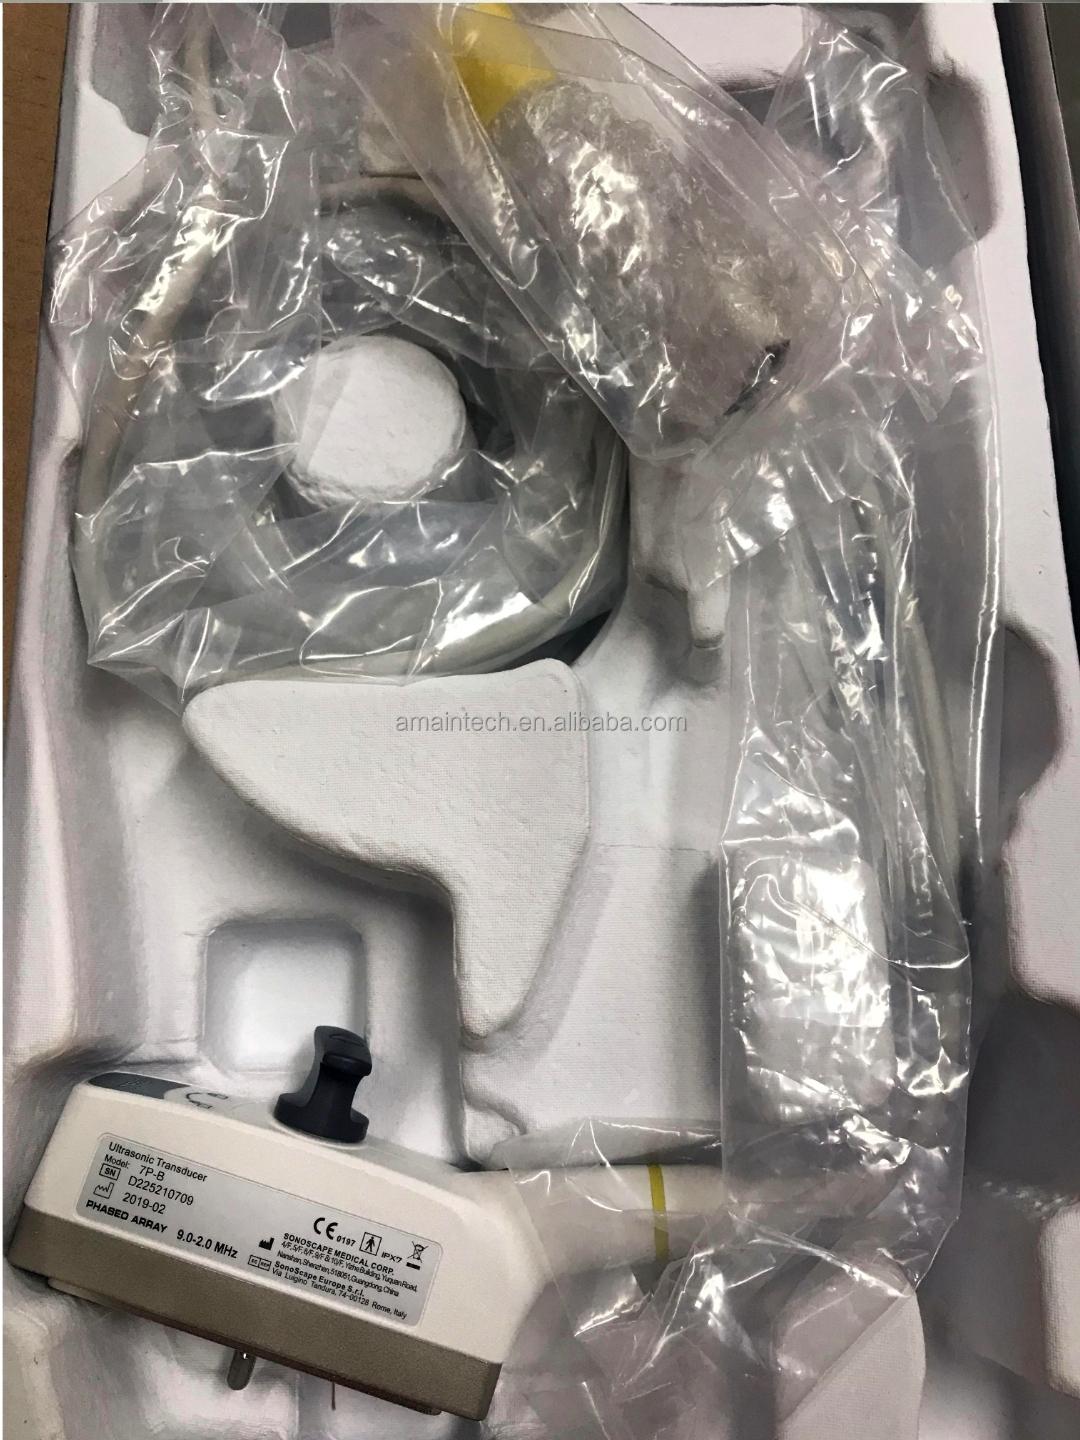

Amain use professional packge for you.table for option.